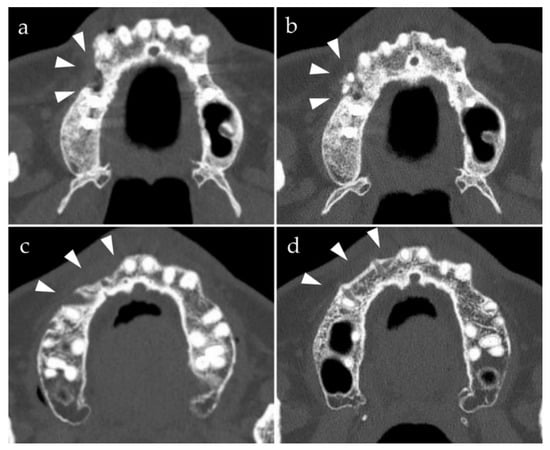

3.1. Clinical Evaluation